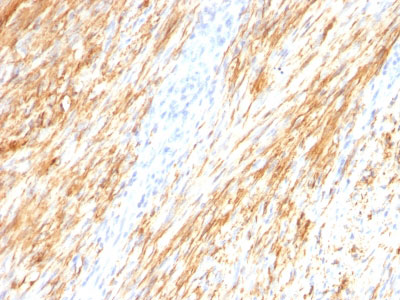

Formalin-fixed, paraffin-embedded human Schwanoma stained with GFAP Monoclonal Antibody (ASTRO/789).